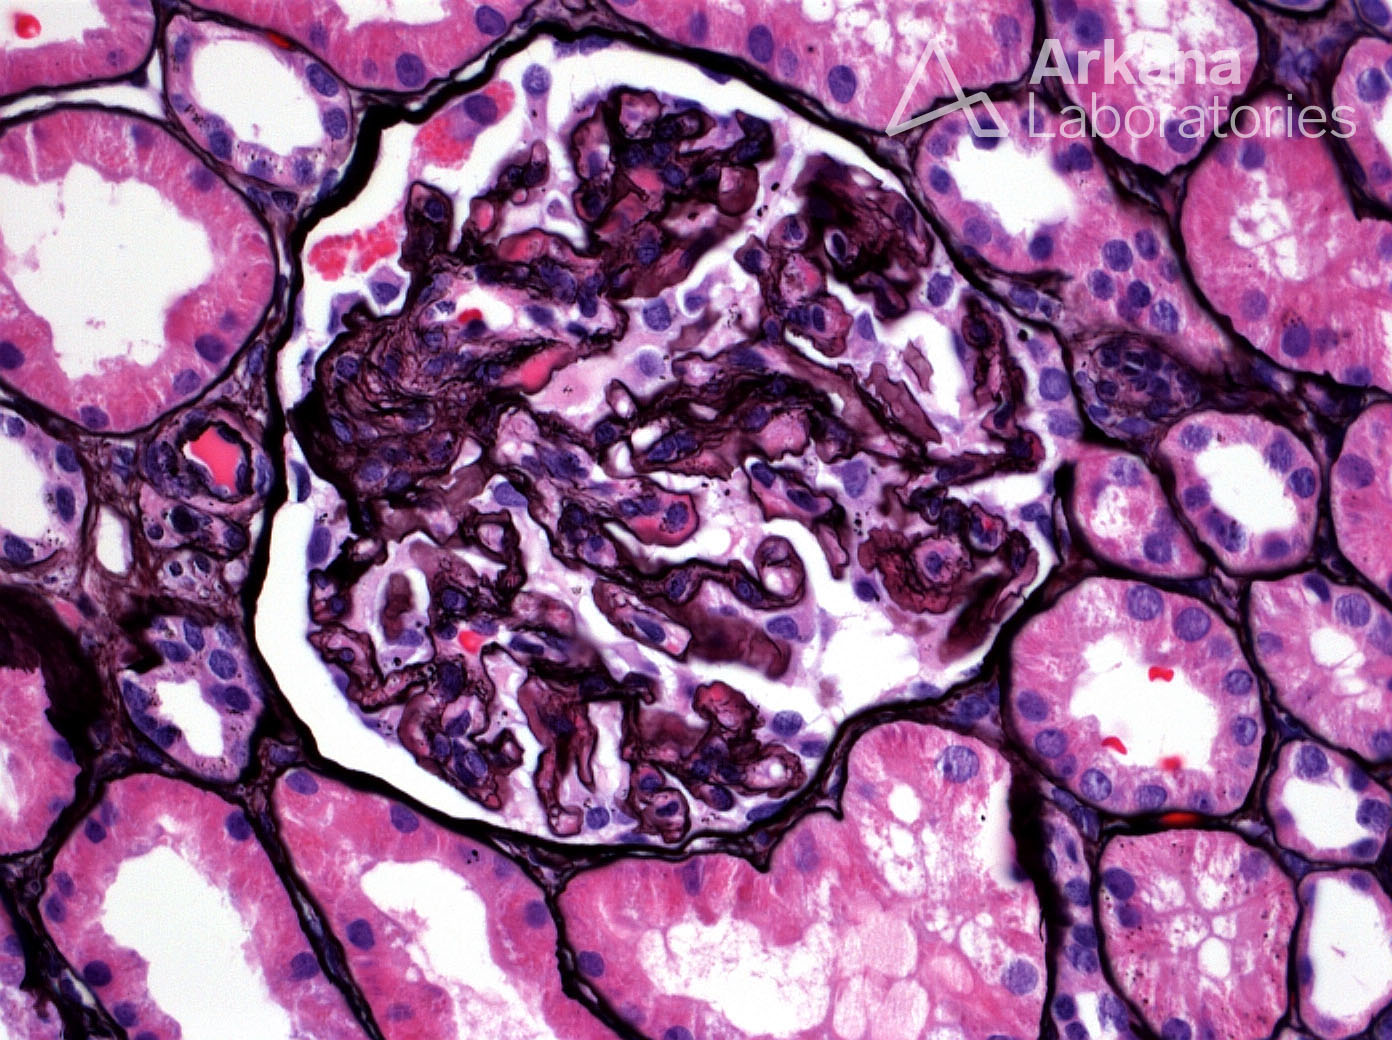

Previous Image Next Image Mesangiolysis, Double Contours and GBM Corrugation in a Patient with Preeclampsia on Jones Silver Like Loading...